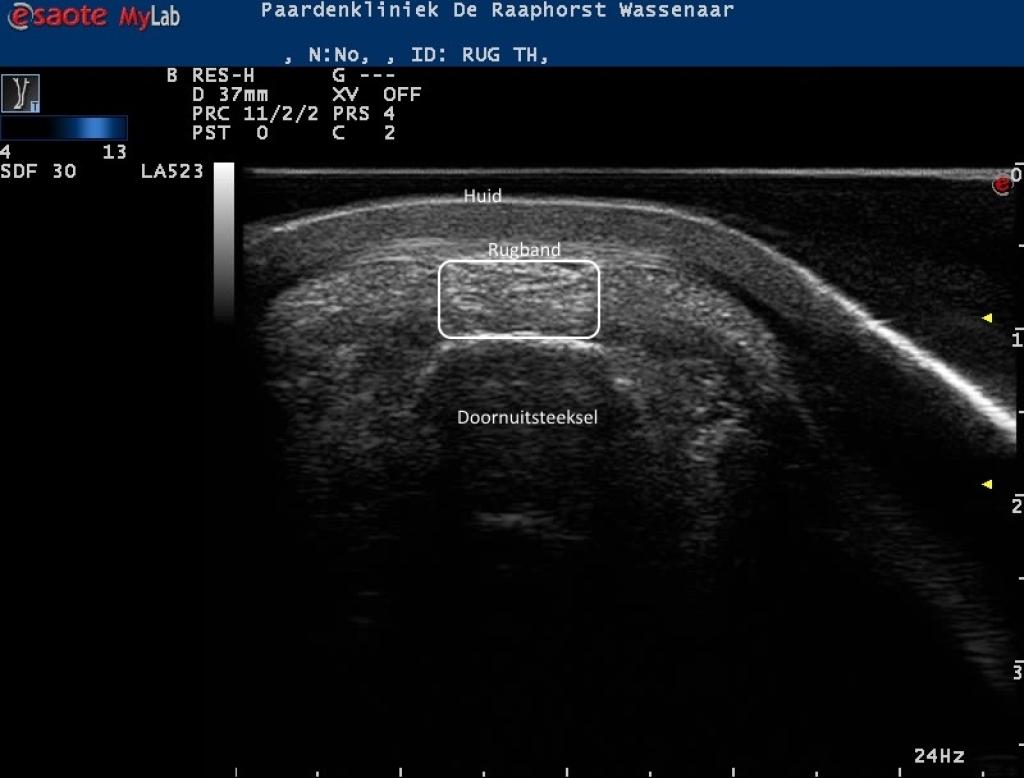

Echobeelden van de lengte en dwarsdoorsnede van de rugband

Foto: Echobeelden van de lengte en dwarsdoorsnede van de rugband